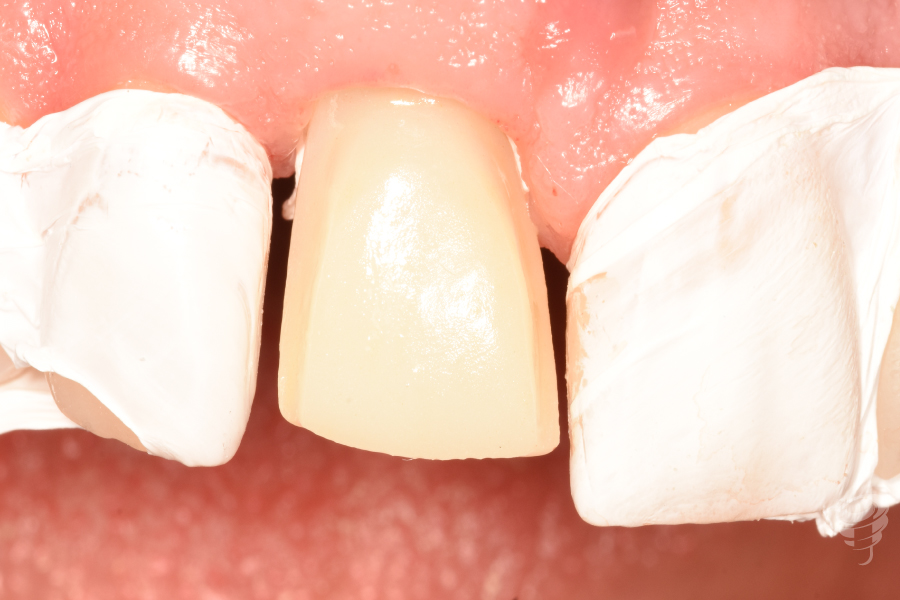

- Restauración definitiva:

Pilar de zirconio ceramizado implanto-soportado monolítico (translucidez media, color A1)

Carillas de disilicato de litio (IPS e.max Press, espesor 0.6mm) de 12 a 21, cementadas con resina dual

Figura 40

Figura 41

Figura 42